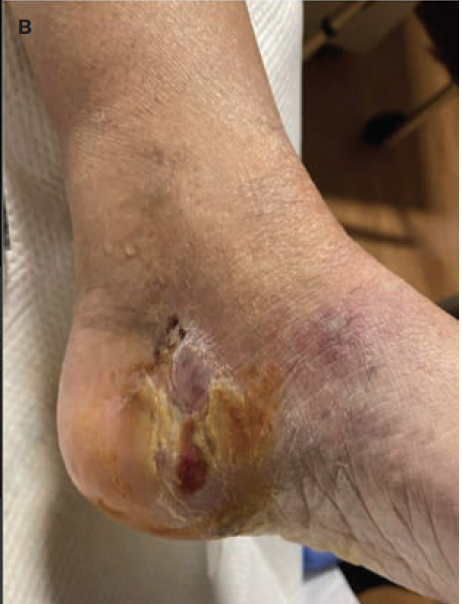

A 64-year-old female presented with an increasingly enlarging wound on the medial aspect of her left heel. She noted no clear etiology for the wound, denying any accident, injury, trauma, or shoe irritation. She had been self-managing the wound with conservative treatments, including topical antibiotic and dry sterile dressings for several weeks without improvement. Past medical history was significant for mild peripheral arterial disease (PAD) with previous stent placement of bilateral iliac arteries (right toe brachial index [TBI] of 0.87 and ankle-brachial index [ABI] of 0.96, and left TBI of 0.65 and ABI of 0.95, with triphasic flow noted to bilateral dorsalis pedis and posterior tibial pulse) and type 2 diabetes mellitus, with the most recent A1c of 5.5%. She was a former 22.5 pack per year smoker and had quit smoking 10 years prior to the onset of this wound. Her diabetes was treated with dapagliflozin 10 mg daily and dulaglutide 0.75 mg once weekly. She was medically managed for her PAD with clopidogrel 75 mg daily, rosuvastatin 40 mg daily, and cilostazol 50 mg twice daily.

At the time of presentation to the authors of this case report, patient had been presenting on a weekly basis to an outside podiatrist for approximately 8 weeks (Figure 1). In addition to receiving care from the outpatient podiatrist, the patient had been following up intermittently with her vascular surgeon, who believed the patient did not need further surgical intervention and deemed her to have “mild arterial disease” at the time of this wound. The patient’s treatment included routine debridement, application of silver-enhanced alginate (ie, silver alginate), and off-loading with a tall controlled ankle motion boot/removable cast walker. During this time, the patient was monitored for signs of osteomyelitis to the left calcaneus with serial foot radiographs and a magnetic resonance imaging (MRI), which showed no evidence of calcaneal osteomyelitis (Figure 2). The patient was also monitored for signs of worsening arterial status to the lower extremities, with no status change during the progression of this wound. She was deemed medically optimized from a vascular surgery standpoint.

Of note, prior to hospitalization with the authors of the present study, there were 3 inpatient hospitalizations due to increased pain, erythema, and swelling during the treatment course. Detailed social and medical history were reviewed. The patient reported no recent travel or sick contacts. She did report a bout of significant depression during which she neglected self-care and household chores, resulting in overall poor housing conditions.